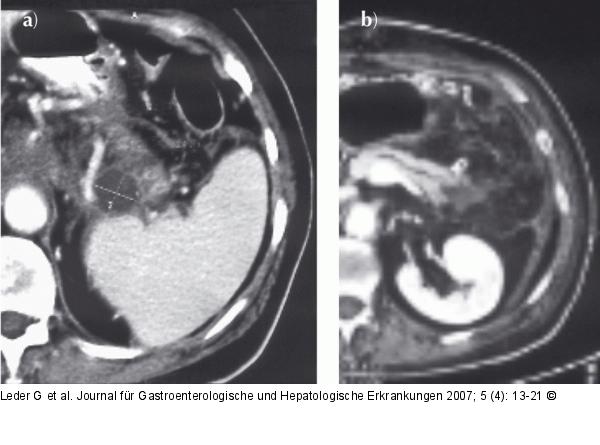

Abbildung 1: Chronische Pankreatitis a) Die CT vom 4.7. 2003 zeigt eine partiell zystische Raumforderung im Pankreasschwanz (eingemessener Durchmesser 2,2 x 1,9 cm), die als Zystadenokarzinom interpretiert wurde, sich letztlich aber als nekrosenhaltige Pseudozyste bei Pankreatitis herausstellte. Zeichen der Pankreatitis sind die aufgelockerte Struktur des Pankreas und seine unscharfe Abgrenzung zur Umgebung. b) Nach Pankreasschwanzresektion zeigt diese am 11.8.2003 zur Abklärung einer postoperativen Blutung angefertigte CT nebenbefundlich einen dilatierten Pankreasgang im Korpus und eine Restnekrose im ehemaligen Pankreasschwanzareal. |